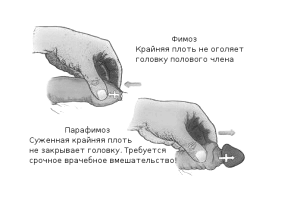

- фимозом,

При набряку і почервоніння голівки, появі хворобливих виразок на ній і крайньої плоті, загальної слабкості та високої температури діагностують гангренозну форму баланопостіта і розвиток фімозу.

- звужується уретра і розвивається фімоз,